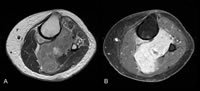

1. ábra Primer tiszta sejtes szarkóma mágneses rezonancia képalkotása.

A tiszta sejtszarkóma jellemzően mágneses rezonancia képalkotás (MRI) segítségével jellemezhető. A T1-súlyozott képek kissé hiperintenzív, homogén tumorjelet mutatnak a közeli izomszövethez képest. T2-súlyozott képek, ahol a víz erősebb jelet ad, mint a zsírszövet, a gadolínium kontrasztot követően nagy intenzitású, különösen a környező izomszövethez képest. Úgy gondolják, hogy a melanin tartalmú tiszta sejtes szarkóma megváltoztathatja az MRI jel intenzitását a többi lágyrész-daganathoz képest, bár ezek a változások nem drámaiak és nem specifikusak ahhoz, hogy önmagában képalkotó diagnózist alkossanak.

Bár a ritka általánosságban, a szinoviális szarkóma (és a Kaposi szarkóma kivételével) a 20-40 éves betegeknél a láb és a boka második leggyakoribb rosszindulatú lágyszöveti daganatáról számoltak be egyértelmű sejtszarkómáról; ezért az anatómiai elhelyezkedés és a megfigyelhető kötődés az inakkal vagy az aponeurosisokkal értékes diagnosztikai tünet lehet a tiszta sejtek szarkóma esetén 10,11 A necrosis vagy a csontos pusztulás ritkán azonosítható, ami a biopsziát megelőző malignus potenciál alulbecsléséhez vezet. 10

Ez a képalkotó technika elsősorban a különböző víz és zsírtartalmú szövetek között különböztet meg. A T1-súlyozott képek fényes jelzéseket mutatnak a zsírszövetre és alacsony jelekre, ahol magas a víztartalom. A T2-súlyozott képek az ellenkezőek, növelve a vízjelet. A csont sötét mindkét típusú MRI képen, ellentétben a sima röntgen- vagy CT-képekkel, ahol a csont fehér. Mivel a lágyszöveti daganatok általában növelik a vérellátást a növekedéshez, gyakran T2-súlyozott képeknél fokozódnak. A gadolínium kontrasztanyagot adjuk be annak érdekében, hogy tovább fokozzuk az erekben lévő víz jelét.